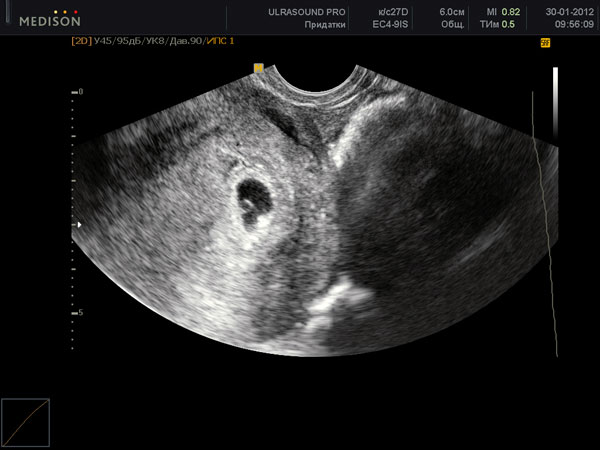

УЗИ на пятой неделе беременности

Если бы беременность не наступила, в этот период у женщины должны были начаться месячные. Их отсутствие, а также первые признаки беременности наводят женщину на мысль сделать тест на беременность, который на этом сроке уже дает положительный результат. Беременность будет очевидна и на УЗИ-обследовании, если его назначит врач.